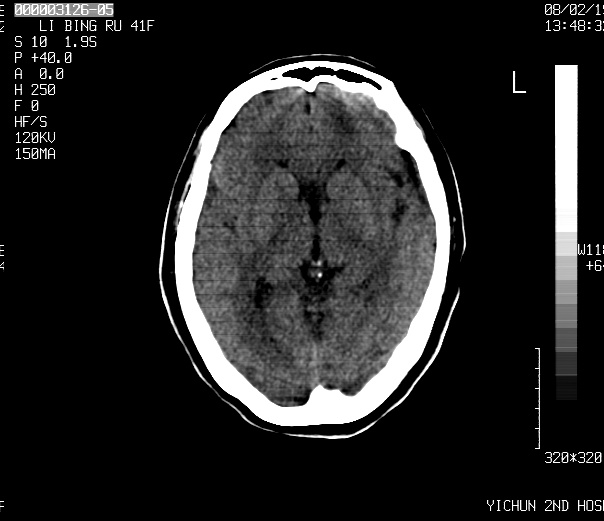

标题: CT11766:女 66岁,请会诊

请各位老师会诊

脑转移瘤

小病灶,大水肿,支持转移瘤。

首先考虑转移瘤!先查个胸部。

多发的占位病变---以小病灶,大水肿为特点,支持转移瘤